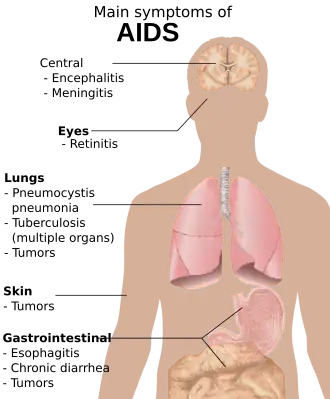

Most AIDS symptoms result from the development of opportunistic infections and cancers associated with severe immunosuppression secondary to HIV.

However, immunosuppression has many other potential causes. Individuals who take glucocorticoids or immunosuppressive drugs to prevent transplant rejection or to treat autoimmune diseases can have increased susceptibility to unusual infections, as do individuals with certain genetic conditions, severe malnutrition and certain kinds of cancers. There is no evidence suggesting that the numbers of such cases have risen, while abundant epidemiologic evidence shows a very large rise in cases of immunosuppression among individuals who share one characteristic: HIV infection.[37][54]

The diseases associated with AIDS, such as Pneumocystis jiroveci pneumonia (PCP) and Mycobacterium avium complex (MAC), are not caused by HIV, but rather result from the immunosuppression caused by HIV disease. As the immune system of an HIV-infected individual weakens, he or she becomes susceptible to the particular viral, fungal, and bacterial infections common in the community. For example, HIV-infected people in the Midwestern United States are much more likely than people in New York City to develop histoplasmosis, which is caused by a fungus. A person in Africa is exposed to pathogens different from individuals in an American city. Children may be exposed to different infectious agents compared to adults.[87]

HIV is the underlying cause of the condition named AIDS, but the additional conditions that may affect an AIDS patient are dependent upon the endemic pathogens to which the patient may be exposed.